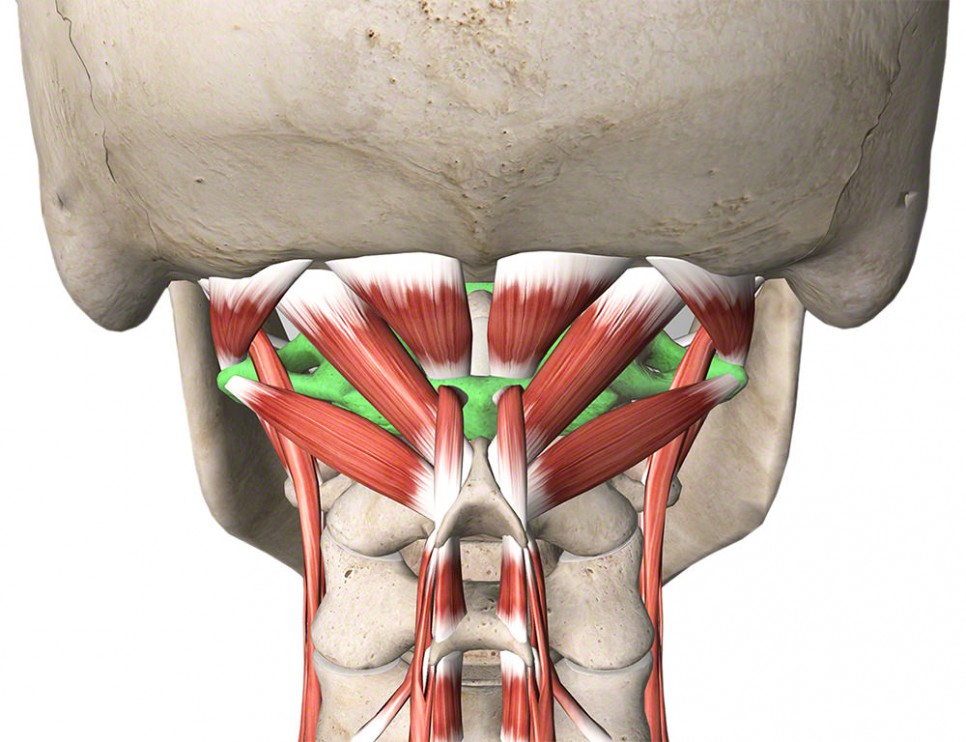

Obr. 3: Krátké extenzory cervikokraniálního přechodu

Cervikogenní bolesti hlavy jsou doprovázeny změnou tonu šíjového svalstva. Významnou roli mají především krátké suboccipitální svaly (krátké extenzory šíje) a jejich přetěžování právě v důsledku předsunutého držení hlavy. Dále jsou přítomny bolestivé spoušťové body v m.sternocleidomastoideus, mm.scaleni, ale také v m.trapezius či m.levator scapulae. Při tlaku na TrP v uvedených svalech bolest vyzařuje do do týla, oblasti spánků nebo temene, někdy až do čelní krajiny či retrobulbárně (za oči).

Dlouhodobé přetěžování krátkých extenzorů šíje směřuje k zatuhnutí skalpu (měkkých tkání na lebce), které rovněž způsobuje silné bolesti hlavy.